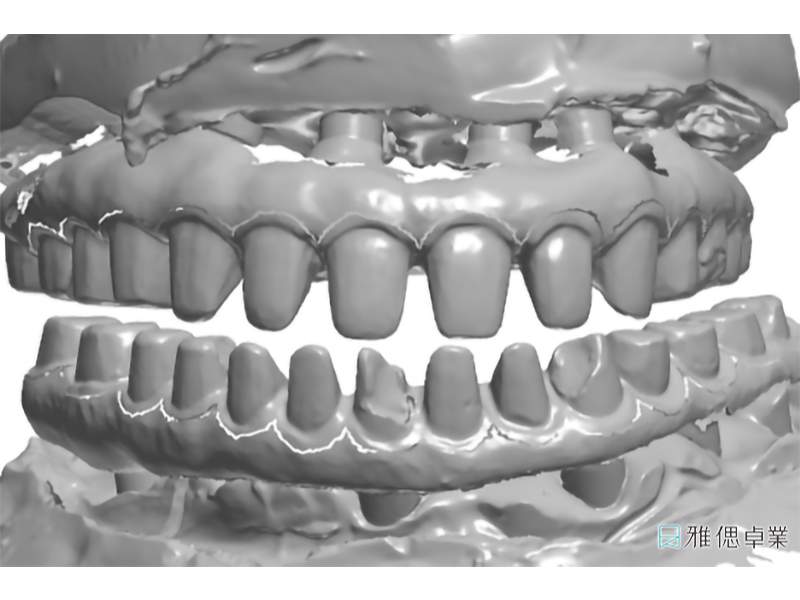

數位軟體設計假牙基座

全口假牙模型,模擬自然牙支台齒

假牙模型上顎

假牙模型下顎